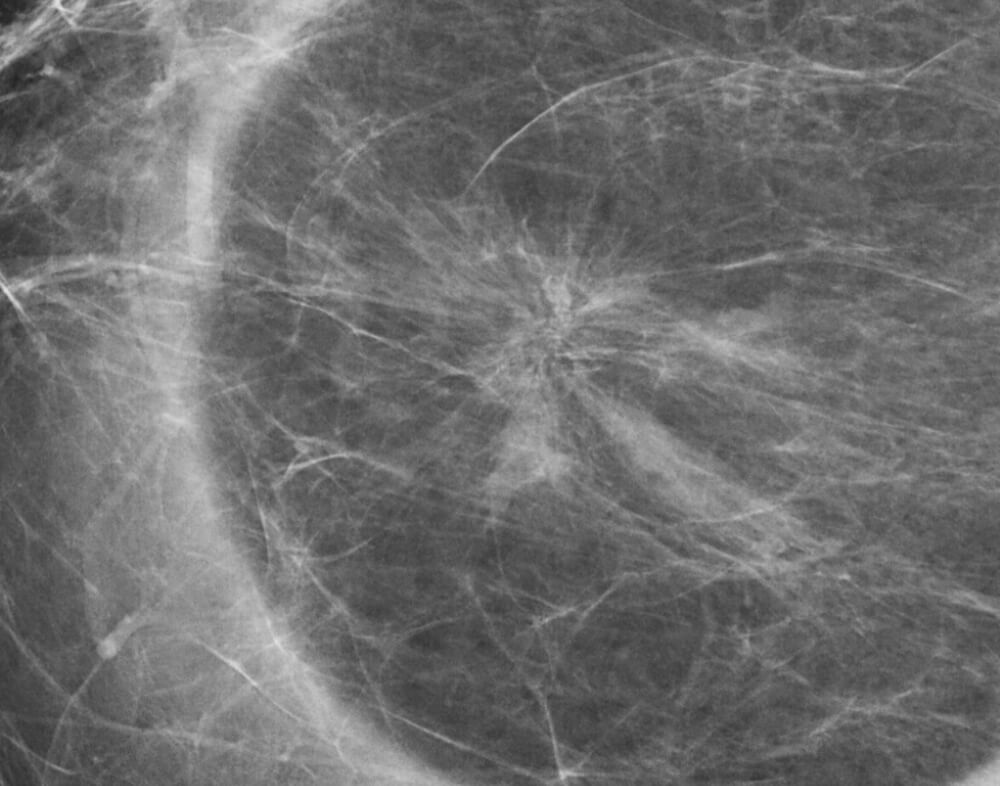

Η ακτινωτή ουλή ή σύνθετη σκληρυντική αλλοίωση είναι μια σχετικά ασυνήθης αλλοίωση του μαστού

και αποτελεί απεικονιστικό εύρημα στο 0.1% των εξετάσεων που γίνονται στον προληπτικό έλεγχο.

Η ακτινωτή ουλή σε πολύ λίγες περιπτώσεις παράγει κλινικό εύρημα το οποίο συνήθως είναι ψηλαφητή σκληρία ή ψηλαφητό ογκίδιο στο μαστό.

Απεικονιστικά (μαστογραφία, υπερηχογράφημα) μιμείται εικόνα καρκινώματος και για το λόγο αυτό η τελική διάγνωση της ακτινωτής ουλής τίθεται μόνο μετά από βιοψία με βελόνη.